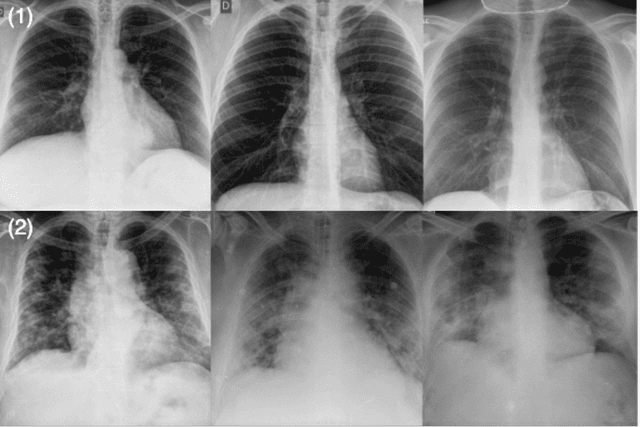

Abstract:As the COVID-19 pandemic continues to devastate globally, the use of chest X-ray (CXR) imaging as a complimentary screening strategy to RT-PCR testing continues to grow given its routine clinical use for respiratory complaint. As part of the COVID-Net open source initiative, we introduce COVID-Net CXR-2, an enhanced deep convolutional neural network design for COVID-19 detection from CXR images built using a greater quantity and diversity of patients than the original COVID-Net. To facilitate this, we also introduce a new benchmark dataset composed of 19,203 CXR images from a multinational cohort of 16,656 patients from at least 51 countries, making it the largest, most diverse COVID-19 CXR dataset in open access form. The COVID-Net CXR-2 network achieves sensitivity and positive predictive value of 95.5%/97.0%, respectively, and was audited in a transparent and responsible manner. Explainability-driven performance validation was used during auditing to gain deeper insights in its decision-making behaviour and to ensure clinically relevant factors are leveraged for improving trust in its usage. Radiologist validation was also conducted, where select cases were reviewed and reported on by two board-certified radiologists with over 10 and 19 years of experience, respectively, and showed that the critical factors leveraged by COVID-Net CXR-2 are consistent with radiologist interpretations. While not a production-ready solution, we hope the open-source, open-access release of COVID-Net CXR-2 and the respective CXR benchmark dataset will encourage researchers, clinical scientists, and citizen scientists to accelerate advancements and innovations in the fight against the pandemic.

Abstract:The world is still struggling in controlling and containing the spread of the COVID-19 pandemic caused by the SARS-CoV-2 virus. The medical conditions associated with SARS-CoV-2 infections have resulted in a surge in the number of patients at clinics and hospitals, leading to a significantly increased strain on healthcare resources. As such, an important part of managing and handling patients with SARS-CoV-2 infections within the clinical workflow is severity assessment, which is often conducted with the use of chest x-ray (CXR) images. In this work, we introduce COVID-Net CXR-S, a convolutional neural network for predicting the airspace severity of a SARS-CoV-2 positive patient based on a CXR image of the patient's chest. More specifically, we leveraged transfer learning to transfer representational knowledge gained from over 16,000 CXR images from a multinational cohort of over 15,000 patient cases into a custom network architecture for severity assessment. Experimental results with a multi-national patient cohort curated by the Radiological Society of North America (RSNA) RICORD initiative showed that the proposed COVID-Net CXR-S has potential to be a powerful tool for computer-aided severity assessment of CXR images of COVID-19 positive patients. Furthermore, radiologist validation on select cases by two board-certified radiologists with over 10 and 19 years of experience, respectively, showed consistency between radiologist interpretation and critical factors leveraged by COVID-Net CXR-S for severity assessment. While not a production-ready solution, the ultimate goal for the open source release of COVID-Net CXR-S is to act as a catalyst for clinical scientists, machine learning researchers, as well as citizen scientists to develop innovative new clinical decision support solutions for helping clinicians around the world manage the continuing pandemic.

Abstract:Tuberculosis (TB) remains a global health problem, and is the leading cause of death from an infectious disease. A crucial step in the treatment of tuberculosis is screening high risk populations and the early detection of the disease, with chest x-ray (CXR) imaging being the most widely-used imaging modality. As such, there has been significant recent interest in artificial intelligence-based TB screening solutions for use in resource-limited scenarios where there is a lack of trained healthcare workers with expertise in CXR interpretation. Motivated by this pressing need and the recent recommendation by the World Health Organization (WHO) for the use of computer-aided diagnosis of TB, we introduce TB-Net, a self-attention deep convolutional neural network tailored for TB case screening. More specifically, we leveraged machine-driven design exploration to build a highly customized deep neural network architecture with attention condensers. We conducted an explainability-driven performance validation process to validate TB-Net's decision-making behaviour. Experiments on CXR data from a multi-national patient cohort showed that the proposed TB-Net is able to achieve accuracy/sensitivity/specificity of 99.86%/100.0%/99.71%. Radiologist validation was conducted on select cases by two board-certified radiologists with over 10 and 19 years of experience, respectively, and showed consistency between radiologist interpretation and critical factors leveraged by TB-Net for TB case detection for the case where radiologists identified anomalies. While not a production-ready solution, we hope that the open-source release of TB-Net as part of the COVID-Net initiative will support researchers, clinicians, and citizen data scientists in advancing this field in the fight against this global public health crisis.